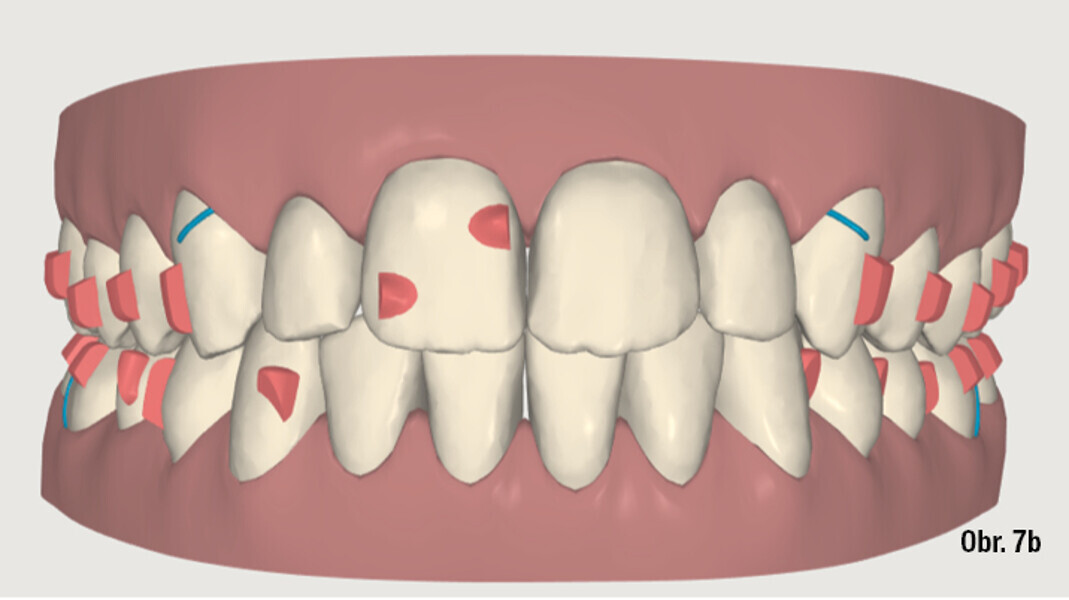

Distalizace horních molárů pomocí alignerů a cyklických sil